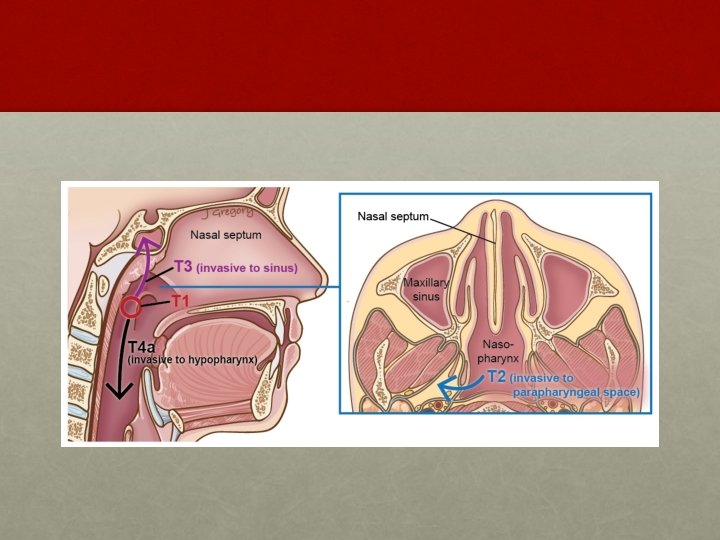

AJCC system: T staging • T 1: • Tumor confined to the nasopharynx • T 2: • Tumor extends to soft tissues • T 2 a : Extends to the oropharynx or the nasal fossa • T 2 b : With parapharyngeal extension • T 3: • Tumor invades bony structures and/or paranasal sinuses • T 4: • Tumor with intracranial extension and/or involvement of cranial nerves, infratemporal fossa, hypopharynx, orbit, or masticator space Department of Radiotherapy, PGIMER, Chandigarh